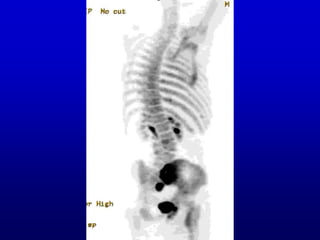

• #36 Standard PET, with activity in heart and liver, hence a more complicated case than the skeleton. You can tell which is left and right. But this is a non-depth-weighted MIP and still subject to some ambiguity. I see it as a case of situs inversus.